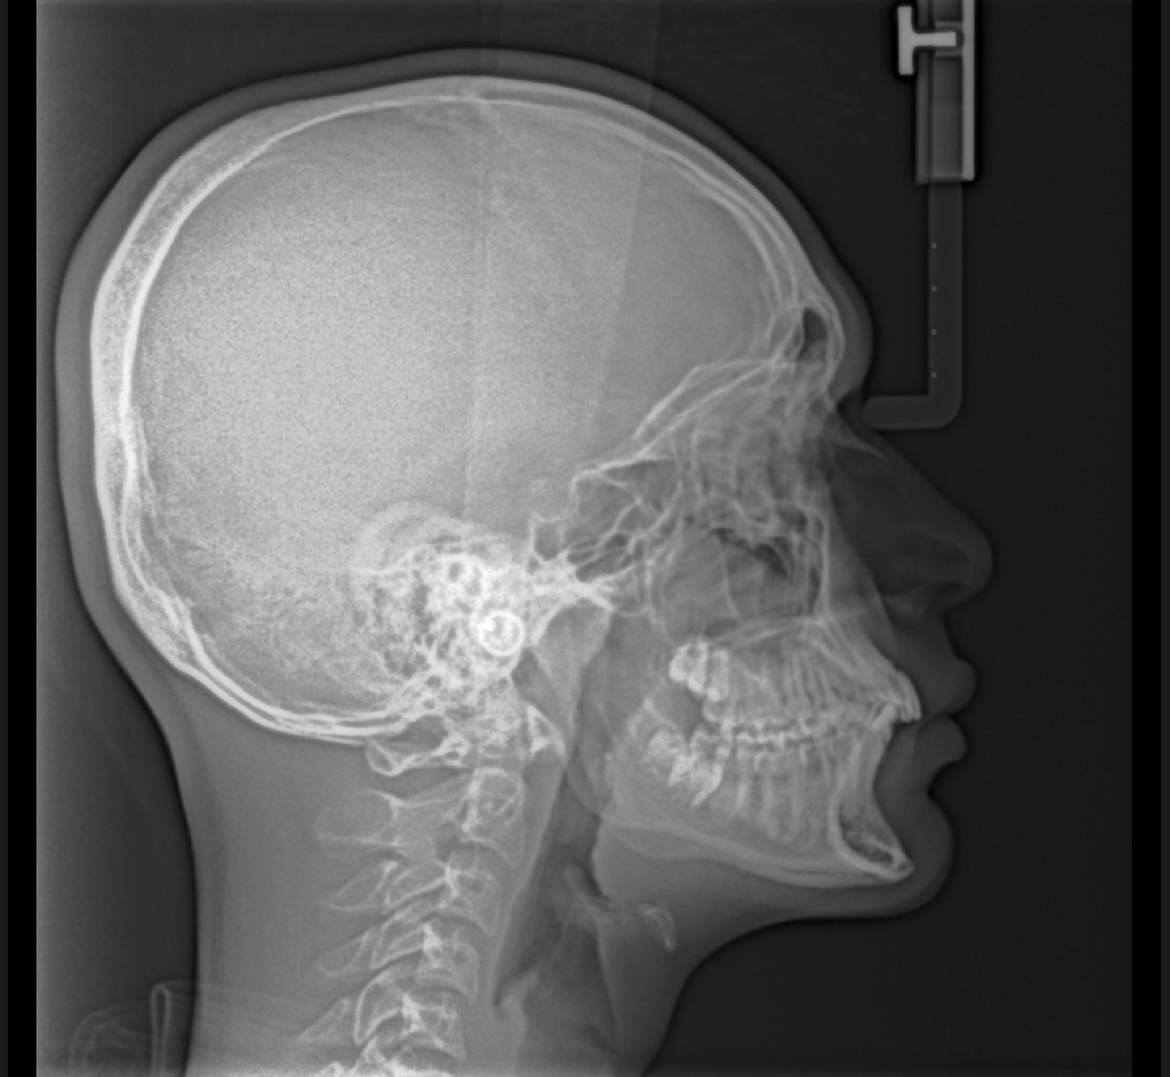

Can anyone read my Lateral Ceph x-rat? How recessed am I?

Also can you measure my SNA and SNB angles

Maxilla & mandible are recessed. You have a class II skeletal tendency(your upper jaw is ahead of the lower) & your chin(both the bone & soft tissue) is also recessed. Your upper & lower incisors are proclined though so it doesn't look so bad(known as a class II camouflage case). Your airway is fine, what's the ceph for bro?

Dang that’s brutal. What’s the solution for it? I’m 18 tho

Honestly could be worse, looks like you have light bimaxillary protrusion. Bimax, but just get braces for now as they'll need to fix your malocclusion.

Thanks. Yeah for now I’ll be getting braces, but idk why my ortho is saying my maxilla and mandible is ok?? What do you think about getting an MSE and braces after that? And are Damon braces better than Invisalign?

And do I need any hardmax other than Bimax? Or bimax will be enough to ascend me?

They say it's ok since they aren't affecting your function or airway, it's only harming you aesthetically.

All braces are better than Invisalign, as for MSE can't really tell from just your lateral ceph but if your palette is narrow and V shaped it's a good step.

For hardmaxx, if you can't afford or don't have the time for a bimax(18-36 months), you can always get a genio/chin implant & a rhino to fix an overly convex profile.